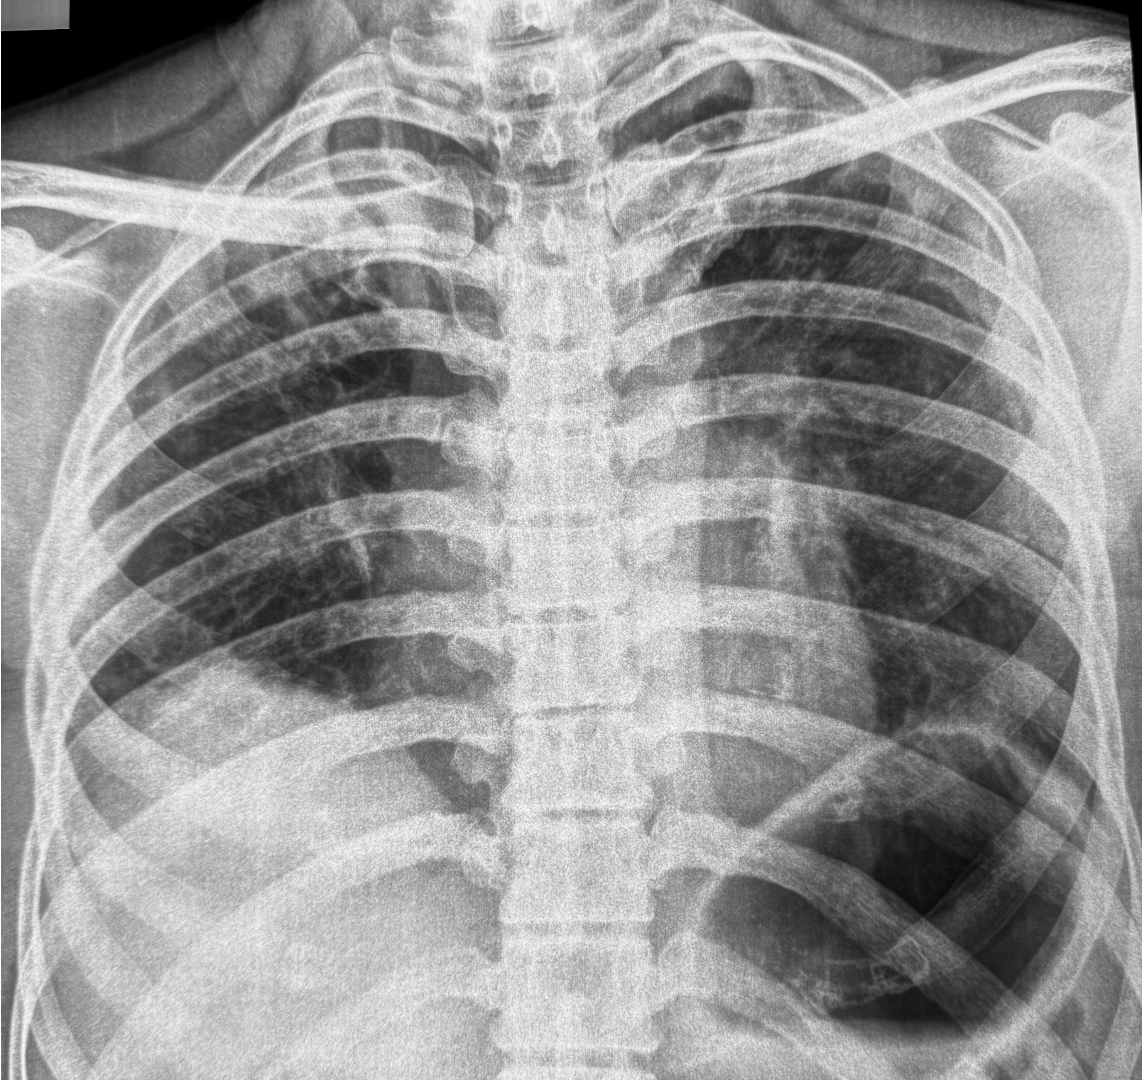

37-years old with gradually progressive dyspnea.

Upper lobe reticular opacities with volume loss, extending below tracheal bifurcation, small left pneumothorax.

CT images show classic findings of pleuroparenchymal fibroelastosis (PPFE), with no other associated etiology, hence idiopathic - iPFFE.

The video describes all the additional findings that often go hand in hand as in

- Playthorax - flat chest - progression of platythorax associated with poorer prognosis

2l Anterior and downward rotation of the ribs - associated with poorer prognosis - Reduced upper lobe lung volumes

- Tracheal deviation and meandering trachea.